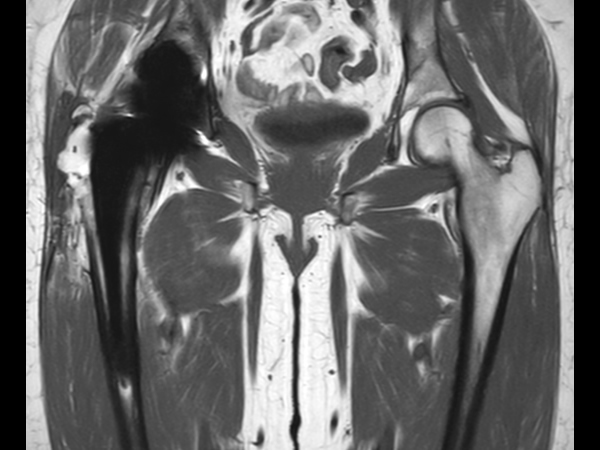

Hip imaging with metal implant

Used Solution

**Only for use with MR Safe or MR Conditional Implants by strictly following the Instructions for Use.